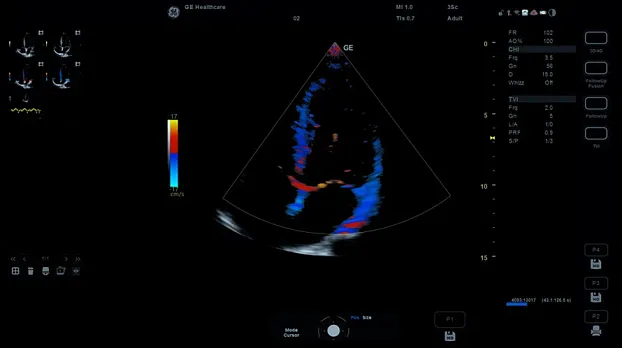

Клинические изображения

- Цветное допплеровское картирование

- Кардиология детская и взрослая